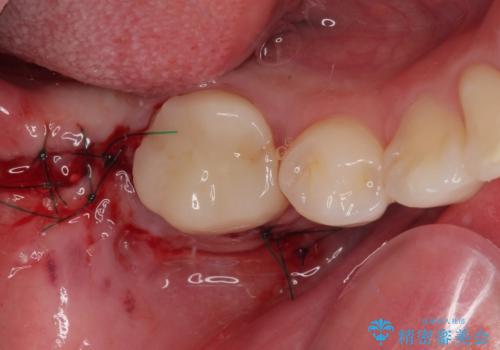

右下の埋伏歯はやはり癒着しており、抜歯の後にインプラントを埋入することとなりました。

埋伏歯の牽引や、奥歯の咬み合わせ改善、インプラント補綴治療と治療期間が延びてしまう要素が多く、治療は難航しましたが、最終的に非常に満足のいく仕上がりとなりました。